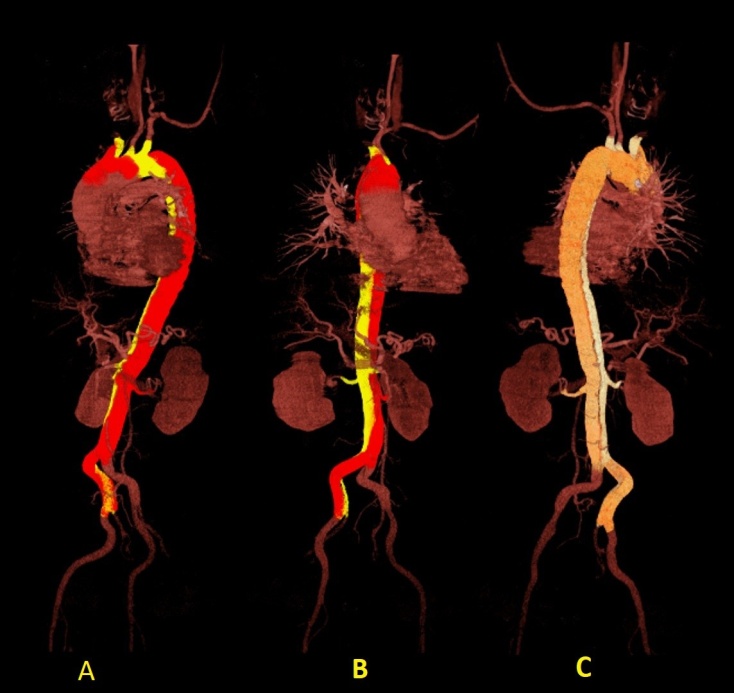

En la tomografía con cortes axial y coronal se observó el colgajo íntimo que dividía la luz aórtica en falsa y verdadera, aunque sin ocluirla. La disección comprometía la aorta ascendente, el arco aórtico, y aorta abdominal, y se extendía a las arterias renal derecha e ilíaca ipsilateral. Se constató derrame pericárdico leve (Fig. 2-4).

Fig. 4 - Reconstrucción angiotomográfica del recorrido de la disección (en A y B, en color amarillo; en C, blanco).